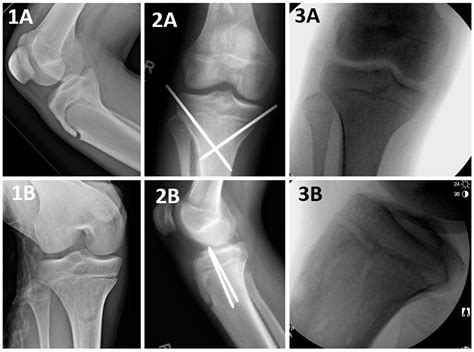

To confirm the diagnosis, medical professionals typically utilize imaging studies. X-rays are the gold standard for visualizing the displaced bone fragment and determining the severity of the fracture. In more complex or comminuted cases, an MRI may be ordered to assess the condition of the surrounding soft tissues, including the patellar tendon and menisci.

Orthopedic surgeons often categorize these injuries based on the Ogden classification system, which helps guide treatment decisions. This classification ranges from simple, non-displaced fractures to complex injuries that extend into the knee joint.

Type Severity Description Typical Treatment

Type I Small fracture at the distal part of the tuberosity. Conservative (casting)

Type II Fracture extends through the secondary ossification center. Surgery often required

Type III Fracture extends into the articular surface of the knee. Surgical intervention

However, if the fragment is displaced or if the knee joint is compromised, surgical intervention is mandatory. The surgical procedure typically involves:

• Open Reduction Internal Fixation (ORIF): The surgeon makes an incision to visualize the bone fragment.

• Hardware Placement: The loose piece of bone is secured back to the main tibia using screws, wires, or specialized anchors.

• pediatric tibial tubercle fracture

• tibial tuberosity fracture radiology